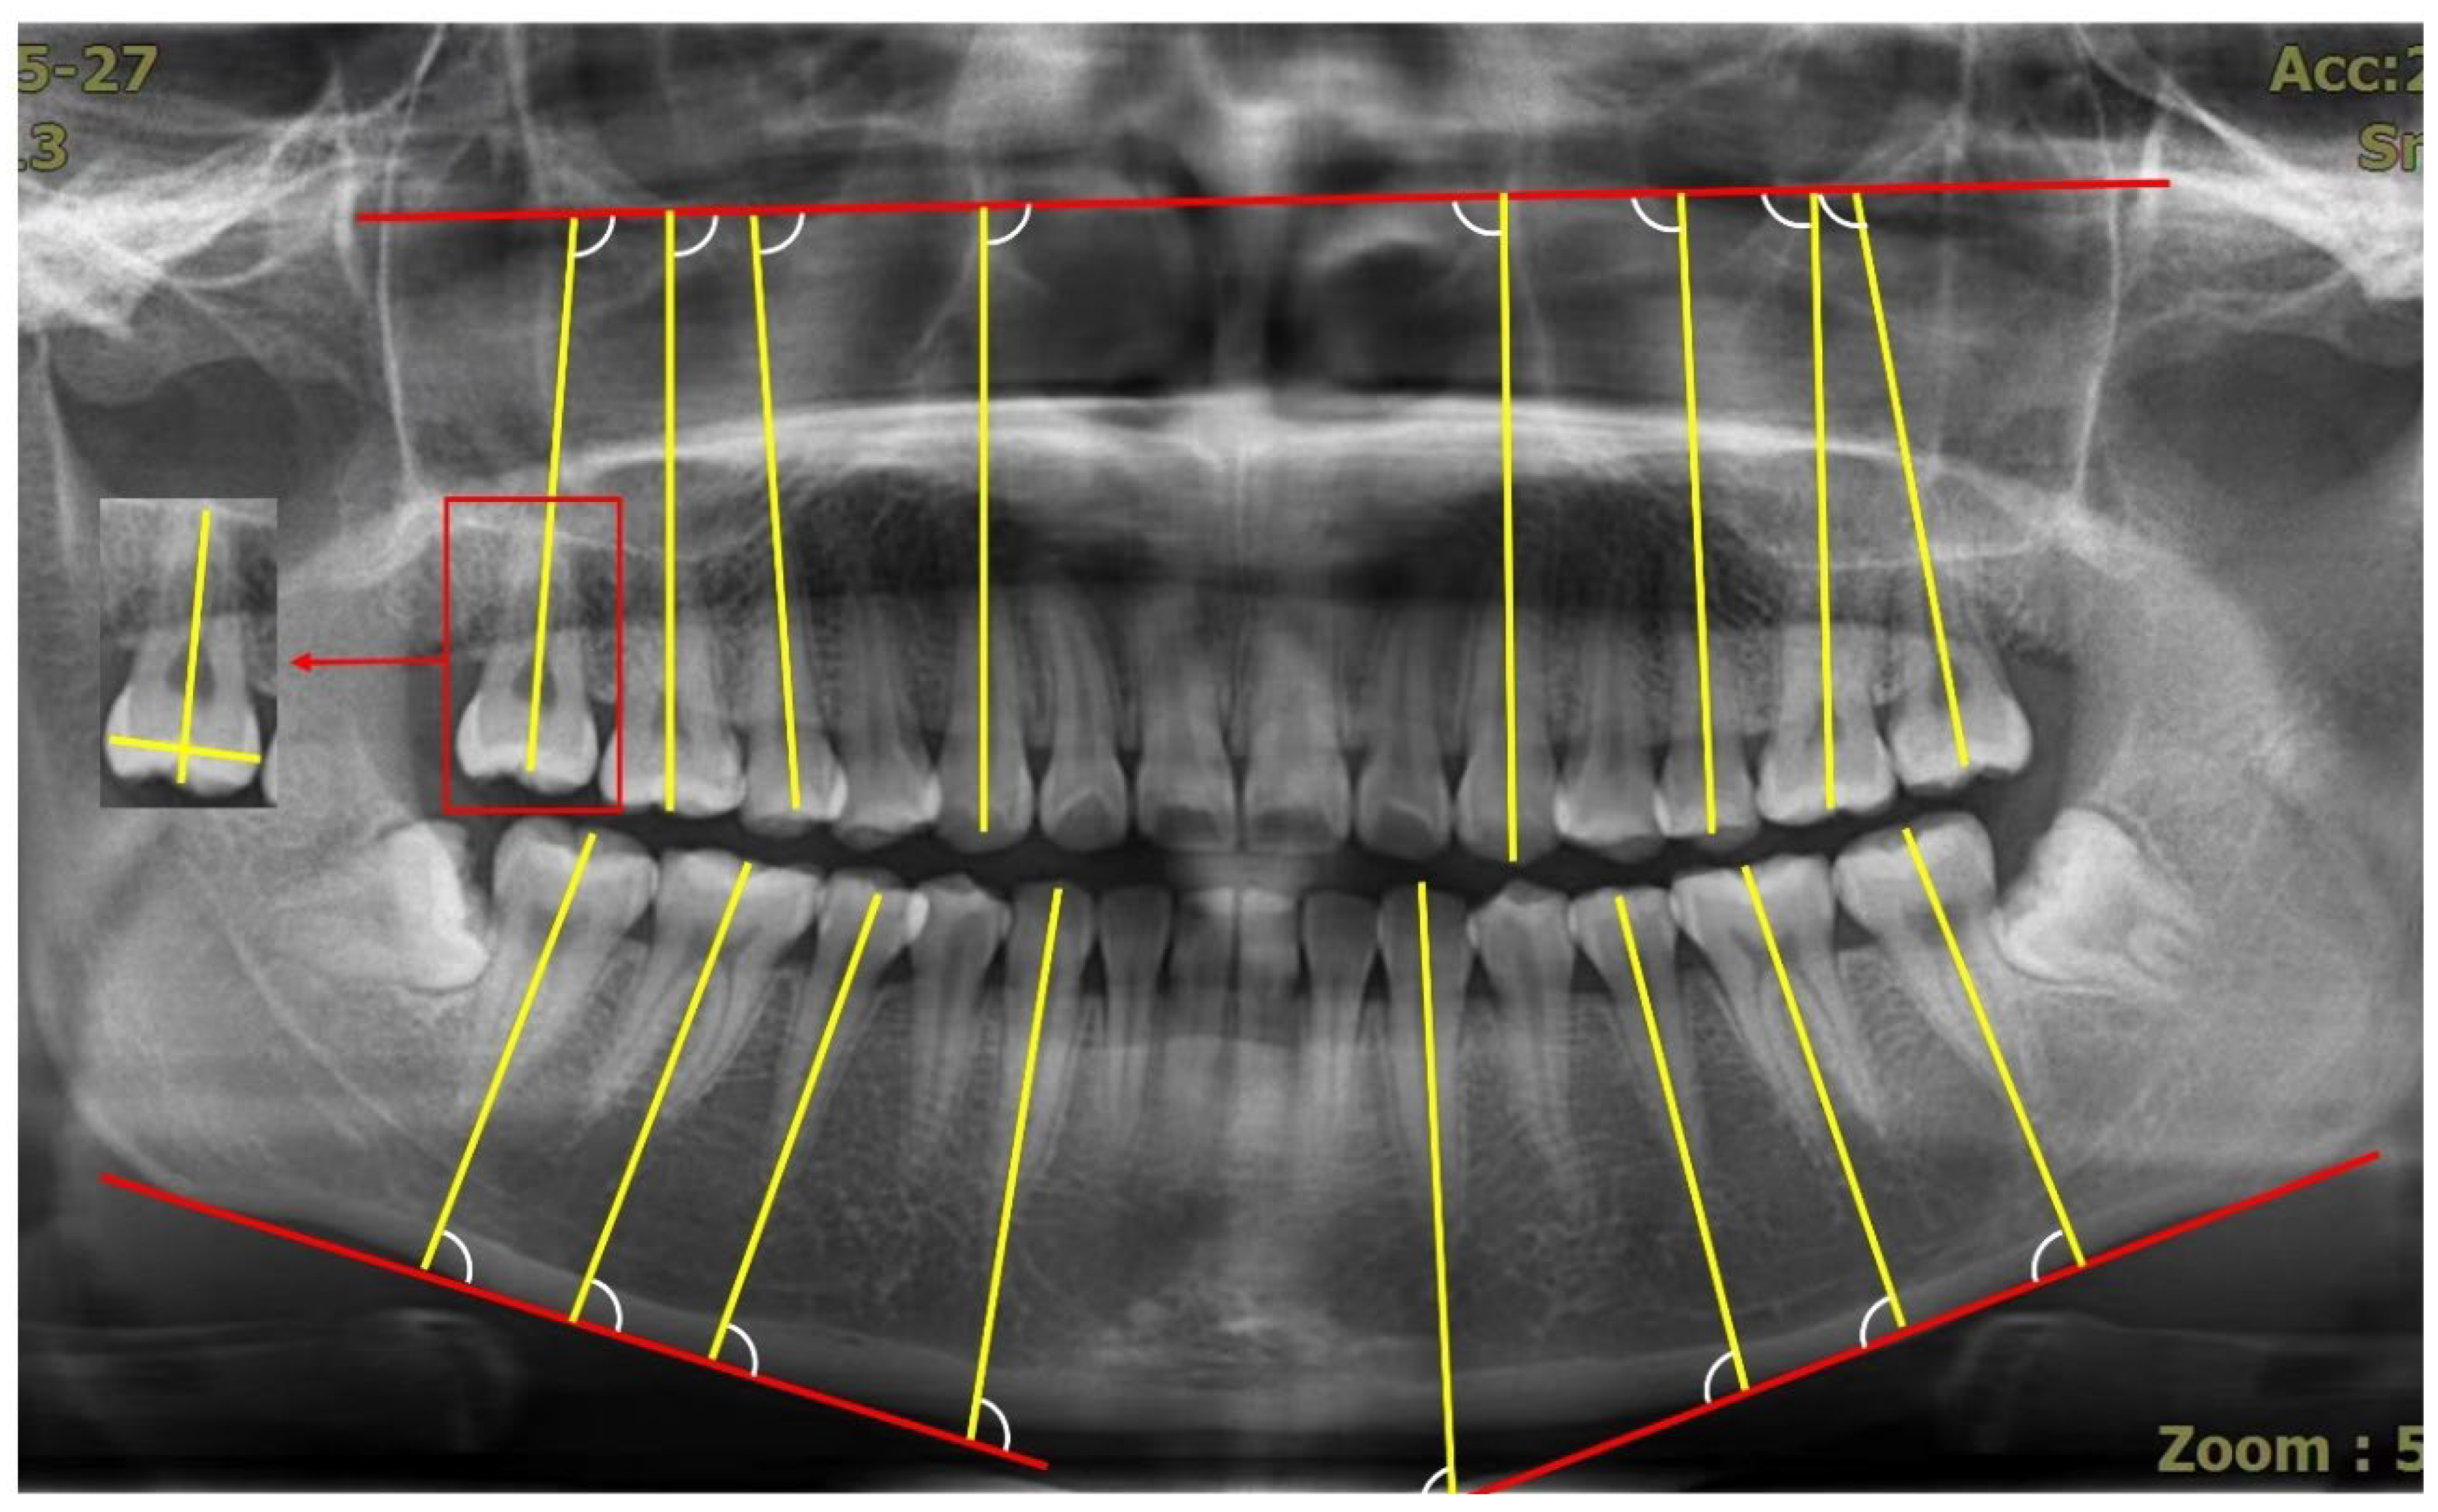

2. Materials and Methods

3. Method of Measurement: